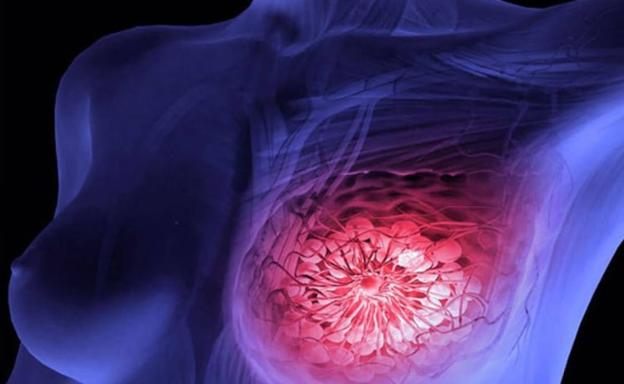

El cáncer le cuesta a los españoles 19.300 millones de euros al año

Reducir al mínimo tabaco, alcohol y obesidad y extender la detección precoz evitaría 55.000 muertes cada año y rebajaría a casi la mitad la factura de esta patología